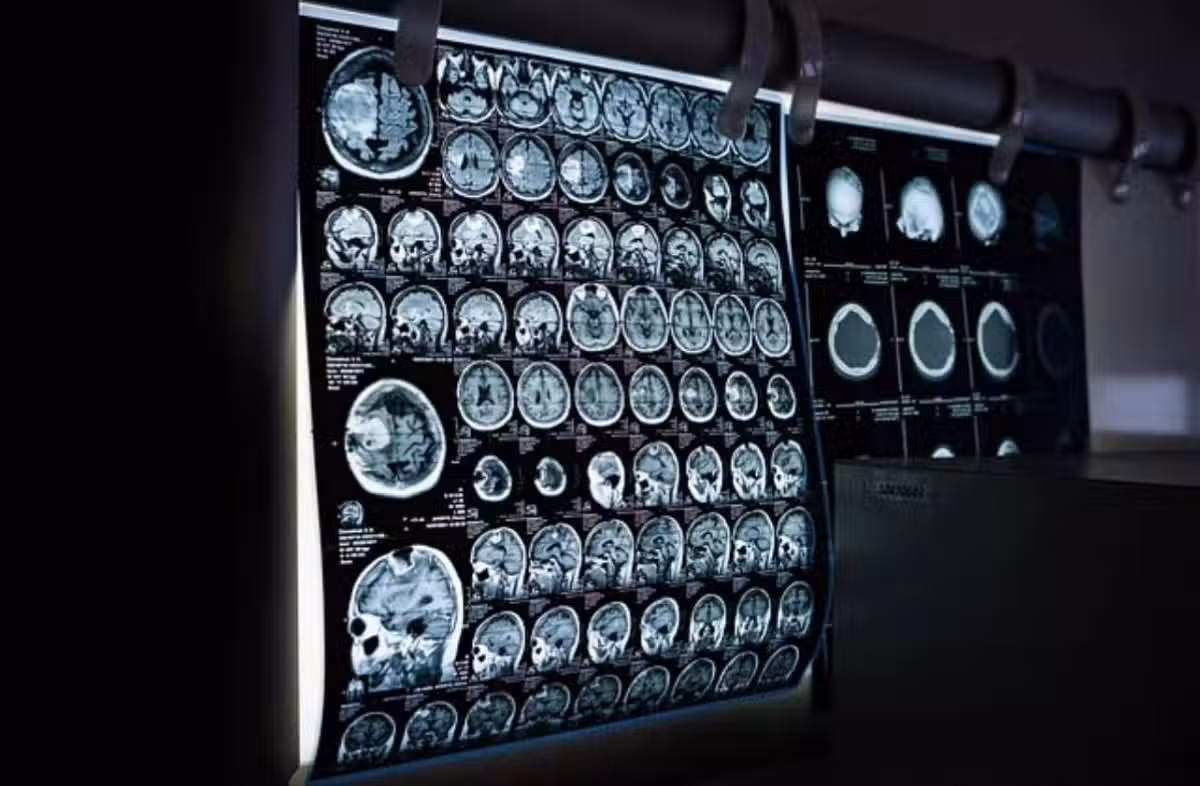

通常做電腦斷層或心導管、血管攝影等檢查,都需要靜脈注射顯影劑,注入體內後需要腎臟代謝,會造成血管收縮使得腎臟短暫的缺血性變化。通常腎功能正常的人不會有太大的影響,但慢性腎衰竭的患者則務必要小心,傷害會在注射後1~2天內出現,腎功能指數最高落在3~5天,通常1-2週內會自行恢復,但有部分四五期的患有,一次一次的注射導致急性腎損傷,尿毒症狀大爆發就開始洗腎。